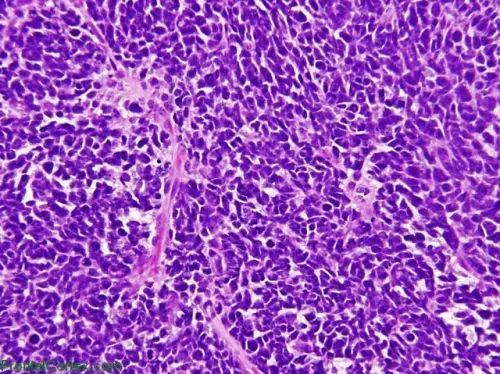

Tumore al Cervello Infantile: Scoperto Meccanismo che lo BloccaE' stato scoperto il modo per bloccare il tumore al cervello più diffuso nei bimbi, il medulloblastoma. Si tratta di uno 'stop molecolare' che ostacola la tremenda patologia

La scoperta è stata fatta da un'equipe di ricercatori dell'Università 'La Sapienza' di Roma e dell'Istituto Pasteur. I medici hanno capito che bisogna colpire il fulcro del meccanismo neoplastico con determinati medicinali. Le prime sperimentazioni hanno avuto esiti confortanti e, vista la loro importanza, sono stati pubblicati sull'autorevole magazine Developmental Cell. Oggi il medullobastoma viene contrastato solamente a livello chirurgico e con radioterapia e chemioterapia. I bimbi che sopravvivono, però, devono spesso affrontare pesanti effetti collaterali. La scoperta fatta recentemente, invece, esclude qualsiasi intervento chirurgico: si incide con farmaci specifici a livello molecolare, ovvero si blocca il meccanismo che favorisce la proliferazione delle cellule tumorali. Esplicative sono indubbiamente le parole di Gianluca Canettieri, responsabile del gruppo di ricerca: "In una percentuale significativa di pazienti il medulloblastoma è causato dall'abnorme attivazione della cosiddetta via di Hedgehog (HH): una sorta di domino molecolare che, in condizioni non controllate, culmina nelle proliferazione e migrazione delle cellule nervose. In questi soggetti abbiamo osservato anche un accumulo di poliammine, cioè piccole molecole a carica positiva che, in genere, aumentano in caso di tumore". Una volta appresa la dinamica, i ricercatori sono intervenuti con medicinali ad hoc, disattivando così le suddette molecole. I primi test, condotti sugli animali, hanno dato risultati entusiastici. Ora toccherà alle sperimentazioni sull'uomo. Speriamo che anche in tal caso i risultati siano confortanti, perché se così fosse si potrebbero delineare terapie personalizzate per determinati tumori.